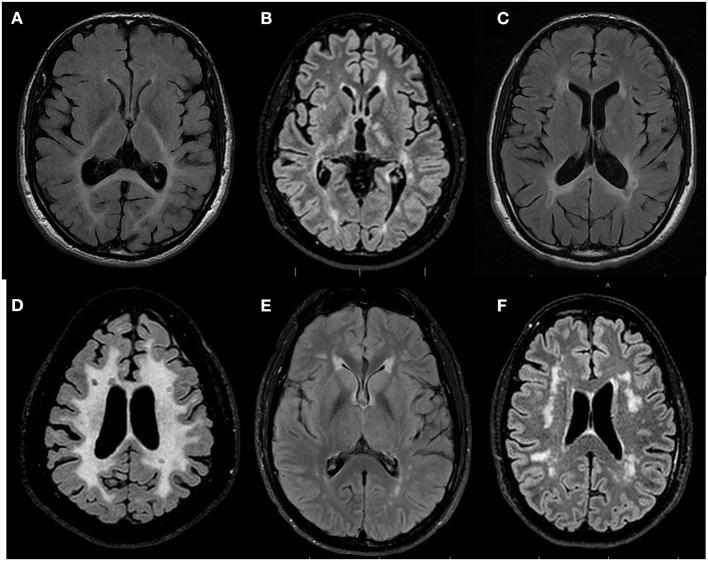

白质病例讨论经验:多学科网络对于加速罕见白质疾病成年患者诊断进程的重要性。

The White Matter Rounds experience: The importance of a multidisciplinary network to accelerate the diagnostic process for adult patients with rare white matter disorders.

Adult genetic leukoencephalopathies are rare neurological disorders that present unique diagnostic challenges due to their clinical and radiological overlap with more common white matter diseases, notably multiple sclerosis (MS). In this context, a strong collaborative multidisciplinary network is beneficial for shortening the diagnostic odyssey of these patients and preventing misdiagnosis. The White Matter Rounds (WM Rounds) are multidisciplinary international online meetings attended by more than 30 physicians and scientists from 15 participating sites that gather every month to discuss patients with atypical white matter disorders. We aim to present the experience of the WM Rounds Network and demonstrate the value of collaborative multidisciplinary international case discussion meetings in differentiating and preventing misdiagnoses between genetic white matter diseases and atypical MS.

成人遗传性白质脑病是罕见的神经系统疾病,由于其临床和影像学表现与更常见的白质疾病(尤其是多发性硬化症(MS))存在重叠,因此在诊断上面临独特挑战。在这种情况下,强大的多学科协作网络有助于缩短这些患者的诊断过程并防止误诊。白质病例讨论会(WM Rounds)是多学科国际在线会议,来自15个参与站点的30多名医生和科学家每月聚在一起,讨论患有非典型白质疾病的患者。我们旨在介绍WM Rounds网络的经验,并展示多学科国际病例协作讨论会在区分和预防遗传性白质疾病与非典型MS误诊方面的价值。